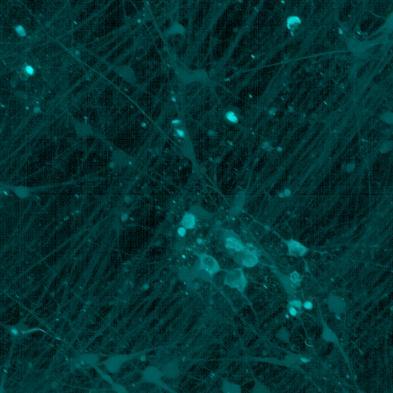

• The transduced neurons were then exposed to tau PFFs and FRET imaging performed

• Increasing over time, PFF exposure induced areas of bright EGFP-positive aggregates of full-length tau, and aggregation of the K18 fragment FRET pair as seen by positive normalised FRET (NFRET) signal

• K18 PFFs with P301L mutation induced aggregation more readily than full length 2N4R PFFs in both systems